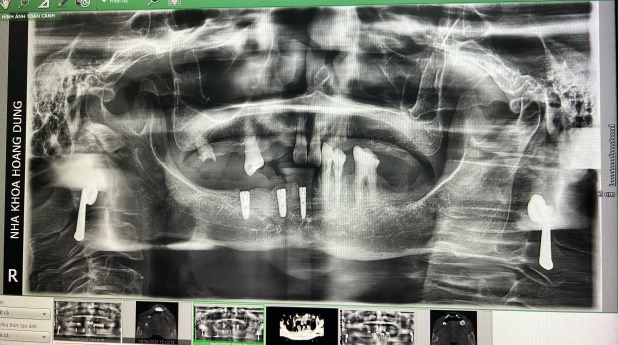

Máy chụp CT Cone Beam 3D là hệ thống chụp X-quang 3D giúp bác sĩ biết chính xác độ rộng, sâu của xương. Ngoài ra, phim chụp X-quang bằng hệ thống Cone Beam CT còn cho thấy rõ mối liên quan giữa răng hàm dưới và dây thần kinh, mối liên quan giữa răng hàm trên và xoang hàm, có thể tầm soát các tổn thương sâu và chi tiết.

Phim 3D CT Cone Beam hỗ trợ đặt implant. Bác sĩ có thể xem mật độ xương để tiên lượng có cần ghép xương hay không và lựa chọn trụ implant có đường kính phù hợp nhất với ổ xương. Thông thường, nếu không có phim 3D Cone Beam CT, bác sĩ sẽ dự đoán đường kính implant bằng cách đo chiều rộng xương theo phương pháp thăm khám lâm sàng hoặc chọn implant có đường kính nhỏ nhất để cấy ghép an toàn. Tuy nhiên, implant sẽ không có tuổi thọ cao. Vì những lý do trên, cấy ghép implant với sự hỗ trợ của máy phim CT Cone Beam 3D sẽ mang lại hiệu quả tốt hơn rất nhiều.

Phim 3D CT Cone beam để đánh giá tương quan giữa răng hàm trên và xoang hàm tránh trường hợp implant bị rơi vào xoang hàm. Mối tương quan giữa răng hàm dưới và dây thần kinh hàm dưới để implant không đè lên dây thần kinh. Đây là thông tin lâm sàng quan trọng để sau khi đặt implant không gây tổn thương.

– Trong khi chụp X-quang toàn cảnh chỉ cho thấy 2 chiều không gian trên và dưới, biết được chiều cao của xương hàm thì 3D CT Cone Beam cho biết được chiều rộng và chiều sâu của xương.

– Phim toàn cảnh chỉ cho thấy hình ảnh của tổn thương, nhưng CT Cone Beam 3D sẽ cho thấy mức độ xâm lấn của tổn thương.

– Đôi khi phim toàn cảnh cho kết quả sai lệch như răng khôn chèn ép dây thần kinh nhưng thực tế khi xem phim CT Cone Beam 3D lại không thấy chèn ép dây thần kinh.